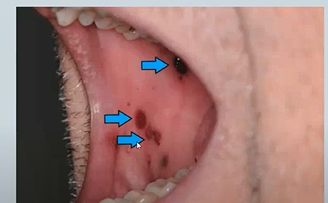

changes in colour of oral mucosa - black or brown 4

Smokers Melanosis - top right - seen in POC - physiological

Melanoma- skin cancer - rare bottom right

Addisons Disease - adrenal insufficiency

Peutz-Jeghers Syndrome - dotted - need to be seen by a GI doctor as theu may experience intestinal polyps